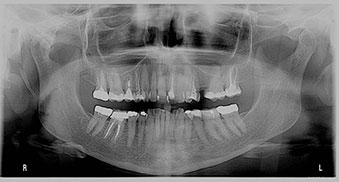

Before any major dental work, a dentist needs to check that your teeth come together properly when you bite and chew. This patient, who faced multiple problems with previous dental treatments, came to our office looking for a solution. The issue was an undiagnosed problem with her bite, which was causing the failure of her dental restorations. By using a specialized bite appliance to understand her bite, we created a plan that helped improve both the function and appearance of her smile.

A 68-year-old woman came to our office with broken teeth and a damaged veneer. She wanted her teeth to look longer, whiter, and prevent further chipping. She was also unhappy with the shape and colour of her front teeth. She had been experiencing bite issues, including jaw discomfort and tooth sensitivity, and had several previous failed dental treatments.